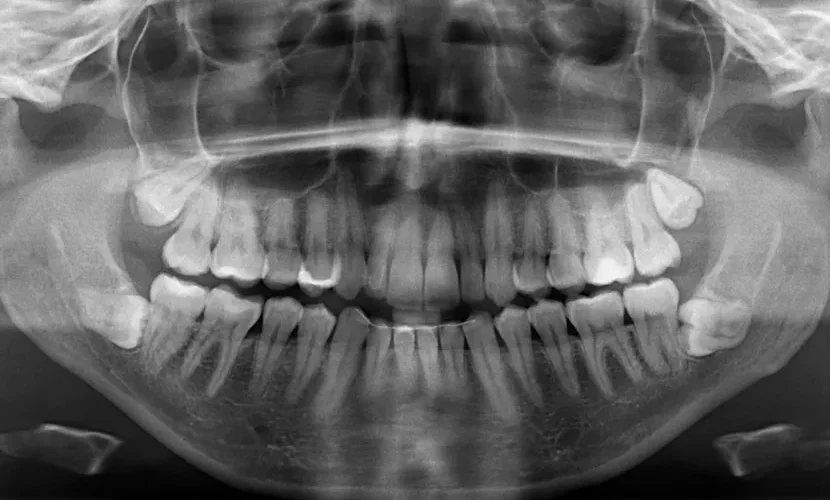

Подоцна, денталната рендгенска снимка покажа дека има уште четири заби кои сè уште не ни изникнале. На почетокот на 2023 година, сфатив дека имам вкупно 42 заби. За среќа, повеќето од забите пораснаа право и без никакви компликации.“

„Луѓето обично се многу изненадени и на почетокот тешко им е да поверуваат, особено кога ќе откријат дека имам 10 заби повеќе од просечната личност, која обично има 32 заби“, рече тој.

Мунијанди додаде дека стоматолозите кои ги прегледале неговите заби за апликацијата за Гинисовата книга на рекорди му дале уште една изненадувачка вест – тој има уште два заба кои сè уште не изникнале. Официјално му е доделена титулата за најголем број заби во машка уста. Женската верзија на рекордот ја држи Калпана Балан од Индија, која има 38 заби.